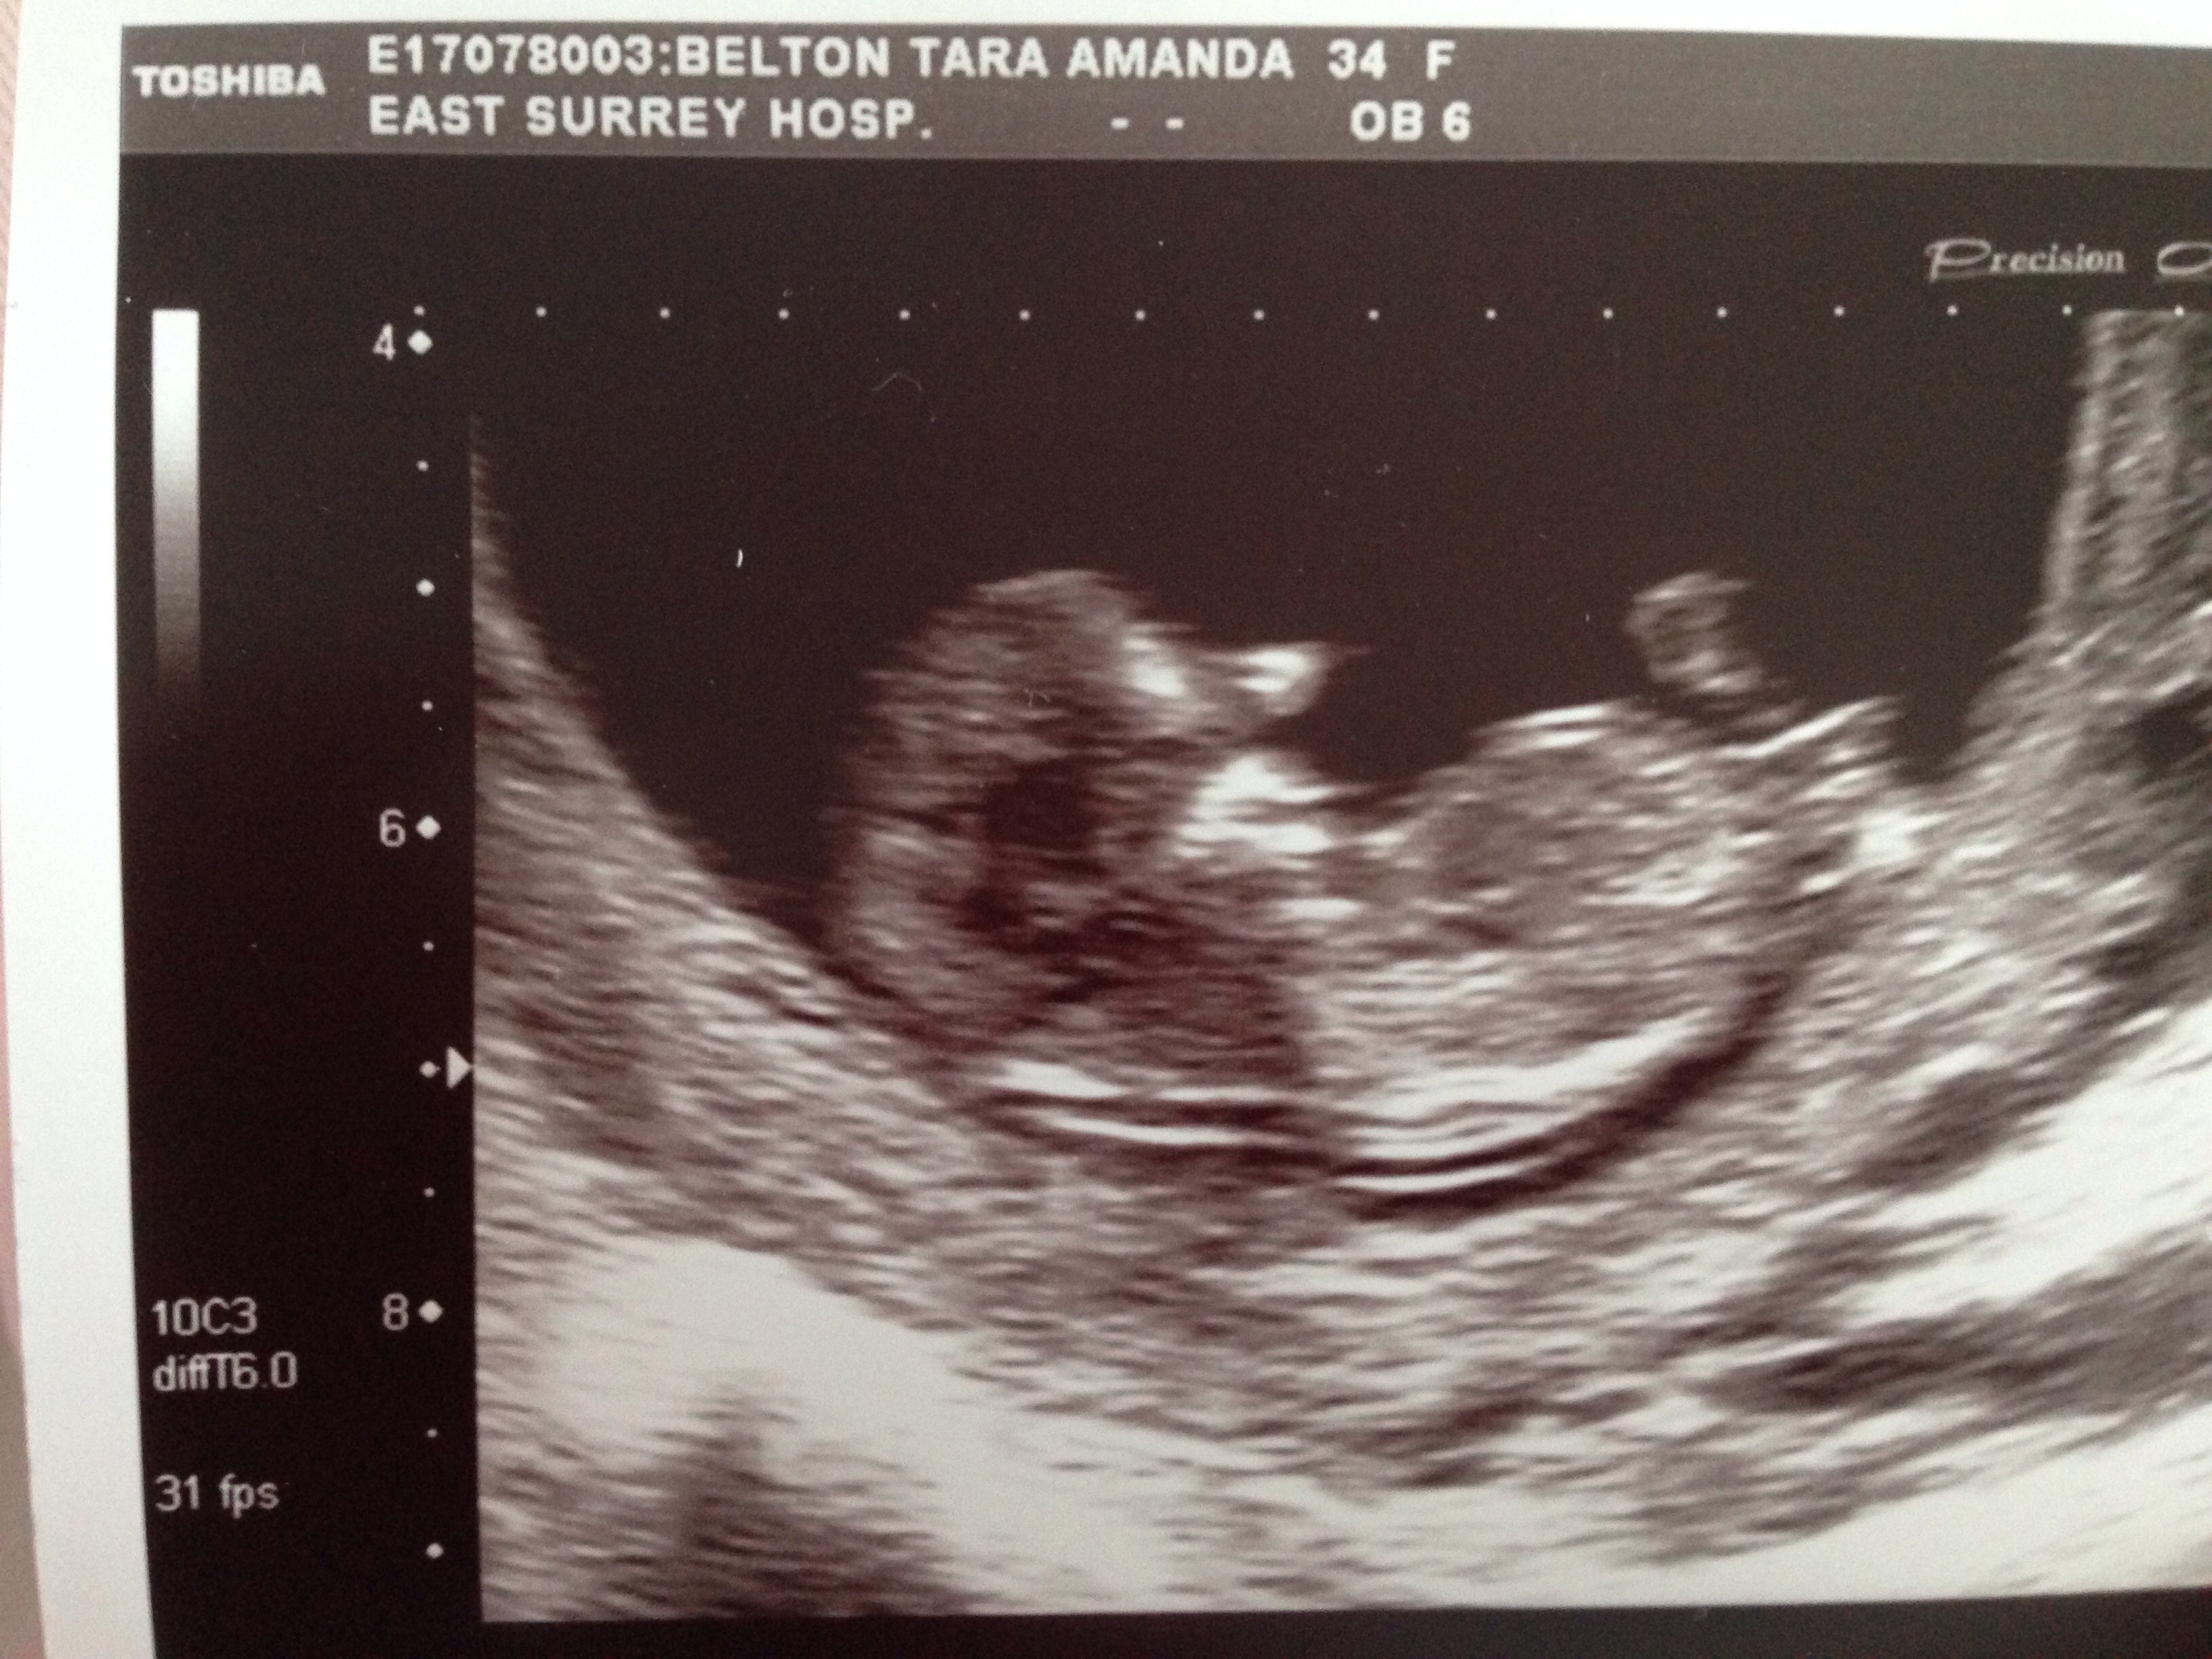

Any guesses with nub theory

Scan 11 weeks and 5 days